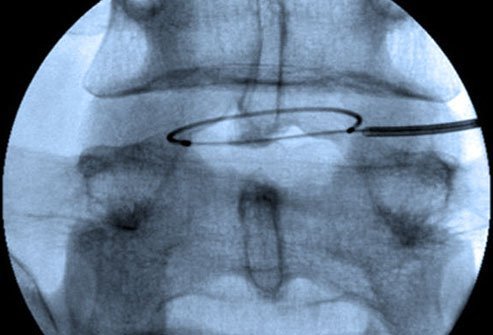

Intradiscal electrothermal therapy (IDET) or intradiscal electrothermal annuloplasty (IDEA), is a minimally invasive technique for the treatment of low back pain caused due to problems with the spinal disc.

IDET introduces a flexible catheter into the disc under fluoroscopic guidance. The catheter is composed of a thermal coil heats the posterior part of the disc, causing contraction of collagen fibers and destruction of the pain receptors.